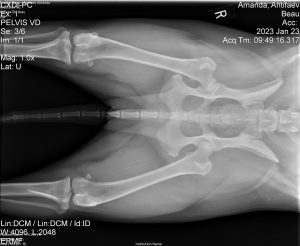

Cranial Cruciate Ligament (CCL) tears are one of the most common causes to hind limb lameness in canines. It is very similar to the ACL in humans. When the CCL tears, the femur and tibia bones slide, creating a draw sign in the stifle joint (knee). This instability damages cartilage leading to osteoarthritis.

This type of an injury is a mechanical lameness and surgery is generally recommended quickly to reduce pain and prevent permanent change to the joint. One such surgical technique to help stabilize the knee joint is Tibial Plateau Leveling Osteotomy (TPLO). TPLO surgery changes the angle of the tibia to the femur, therefore reducing the sliding or draw in the knee joint, stabilizing the knee and preventing osteoarthritis.